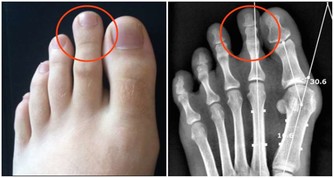

治療風熱感冒、防治腎結石、袪痰、補鈣、